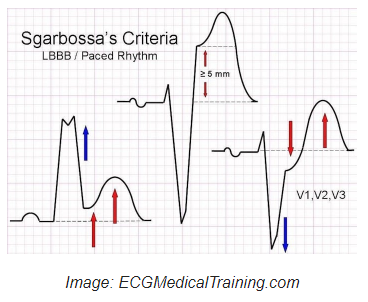

LBBB 환자에서 심근경색을 진단하는 original Sgarbossa Criteria는 다음과 같습니다.

편의상 A, B, C라고 할 때, A와 B는 심근경색에 특이적입니다. 3점 이상일 때 특이적인데 어느 leads에서라도 ST 상승이 1 mm 이상이거나 V1-V3에서 ST 하강이 1 mm 이상인 경우입니다.

A. Concordant ST elevation > 1mm in leads with a positive QRS complex (score 5)

B. Concordant ST depression > 1 mm in V1-V3 (score 3)

C. Excessively discordant ST elevation > 5 mm in leads with a -ve QRS complex (score 2).

C에 해당하는 경우인 어느 leads에서라도 > 5 mm 상승인 것은 특이도가 떨어져 modified Sgarbossa Criteria가 제안되었고 ST deviations > 5 mm 대신 선행하는 S파에 대한 ST 상승이 > 25%인 것으로 정의하였습니다.

Modified Sgarbossa Criteria:

A. ≥ 1 lead with ≥1 mm of concordant ST elevation

B. ≥ 1 lead of V1-V3 with ≥ 1 mm of concordant ST depression

C. ≥ 1 lead anywhere with ≥ 1 mm STE and proportionally excessive discordant STE, as defined by ≥ 25% of the depth of the preceding S-wave.